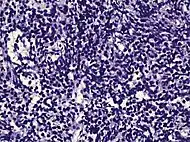

| Urothelial carcinoma | 0.7 to 2.8%[12] | ![]() |

|

Not recommended[1] | |||